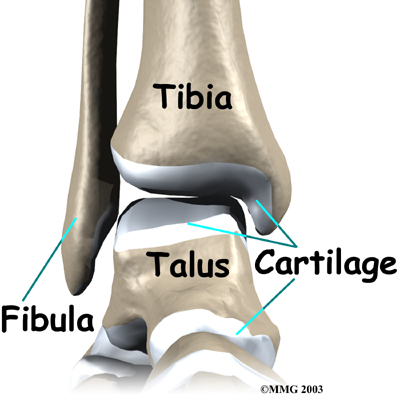

The ankle joint is formed by the connection of three bones. The ankle bone is called the

talus. The top of the talus fits inside a socket that is formed by the lower end of the

tibia (shinbone) and the

fibula (the small bone of the lower leg). The bottom of the talus sits on the heelbone, called the

calcaneus.

The talus works like a inside the socket to allow your foot to move up (dorsiflexion) and down (plantarflexion).

Inside the joint, the bones are covered with a slick material called articular cartilage. Articular cartilage is the material that allows the bones to move smoothly against one another in the joints of the body.

The lining is about one-quarter of an inch thick in most joints that carry body weight, such as the ankle, hip, or knee. It is soft enough to allow for shock absorption but tough enough to last a lifetime, as long as it is not injured.